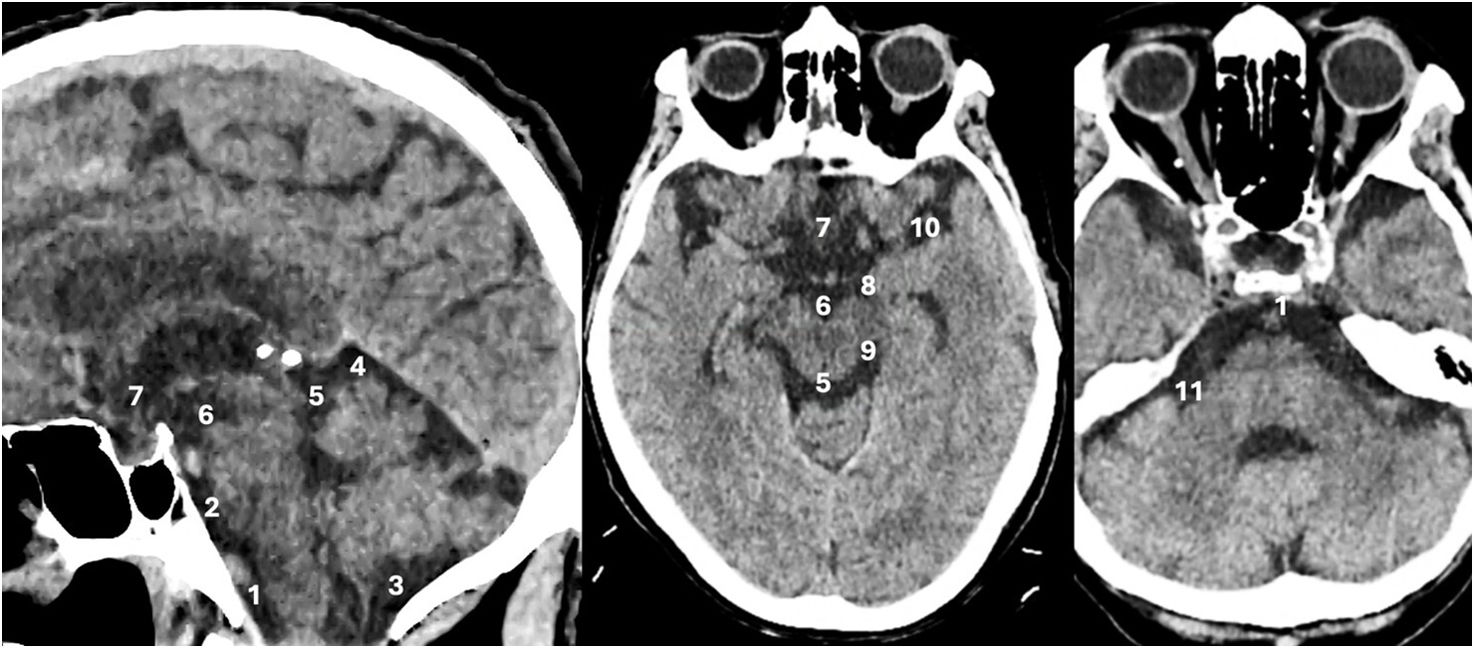

Spontaneous subarachnoid haemorrhage (SAH) is a neurological emergency that predominantly affects young adults, with a high mortality rate and severe neurological sequelae in survivors. Its most characteristic clinical manifestation is a sudden thunderclap headache, often described as the worst headache of one's life, and frequently accompanied by altered levels of consciousness and neck stiffness. Non-contrast cranial computed tomography (NCCT) is the initial diagnostic tool of choice due to its high sensitivity. Recognising the distribution patterns of haemorrhage on NCCT helps guide the aetiological diagnosis and assess the presence of complications such as hydrocephalus, intraventricular haemorrhage or cerebral oedema. This article offers a practical and detailed imaging-based guide for radiologists in the hyperacute phase of spontaneous SAH, distinguishing between aneurysmal, perimesencephalic and cortical patterns, and discusses their clinical, diagnostic and therapeutic implications.